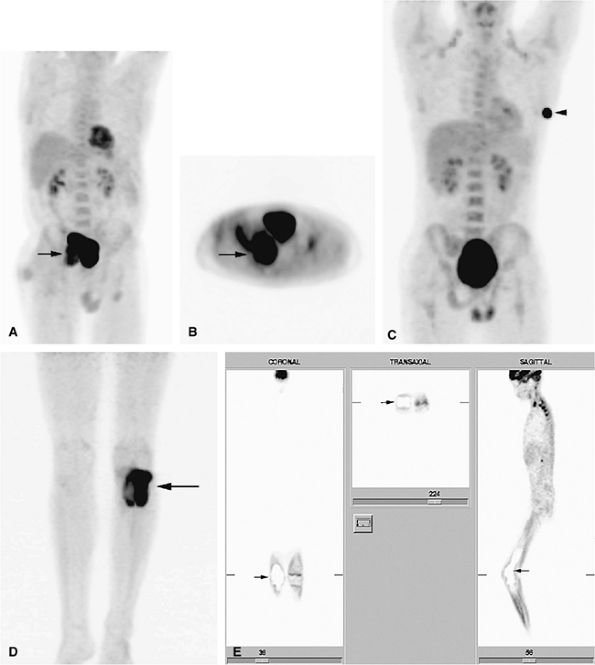

![]() |

FIGURE 14-5 ● FDG-PET in the evaluation of patients with sarcomas. Whole-body FDG-PET scan (A) and corresponding axial image (B) in a patient with neurofibromatosis type 1 demonstrates a region of intense FDG uptake in the right buttock area (arrow), which was found to represent a malignant peripheral nerve sheath tumor arising in a neurofibroma. (C and D) Images from a whole-body FDG PET scan in a patient with osteosarcoma show intense FDG uptake in the proximal tibia (D) in the area of the tumor (arrow). Images of the chest and abdomen demonstrate no evidence of metastatic disease. A marker was placed over the left chest wall (C) (arrowhead). (E) Coronal, axial, and sagittal images of a whole-body FDG-PET scan in a patient with osteosarcoma of the right femur. The patient underwent resection of the right femur and total knee arthroplasty. MR images and CT scans were deemed inadequate for tumor evaluation because of metallic artifact. FDG-PET scan shows a cold defect in the region of the right knee arthroplasty (arrows) and no increased FDG uptake in the area of the right femur and knee.